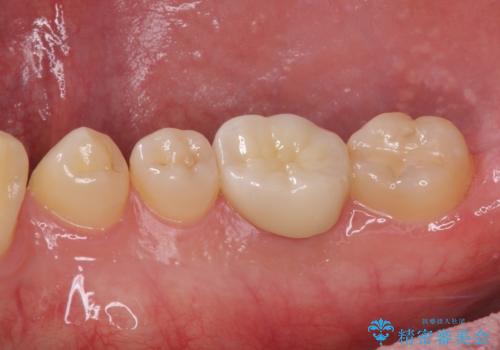

長年気にしていた銀歯を自然な色合いのセラミッククラウンに仕上げることができ、患者様には大変満足していただきました。